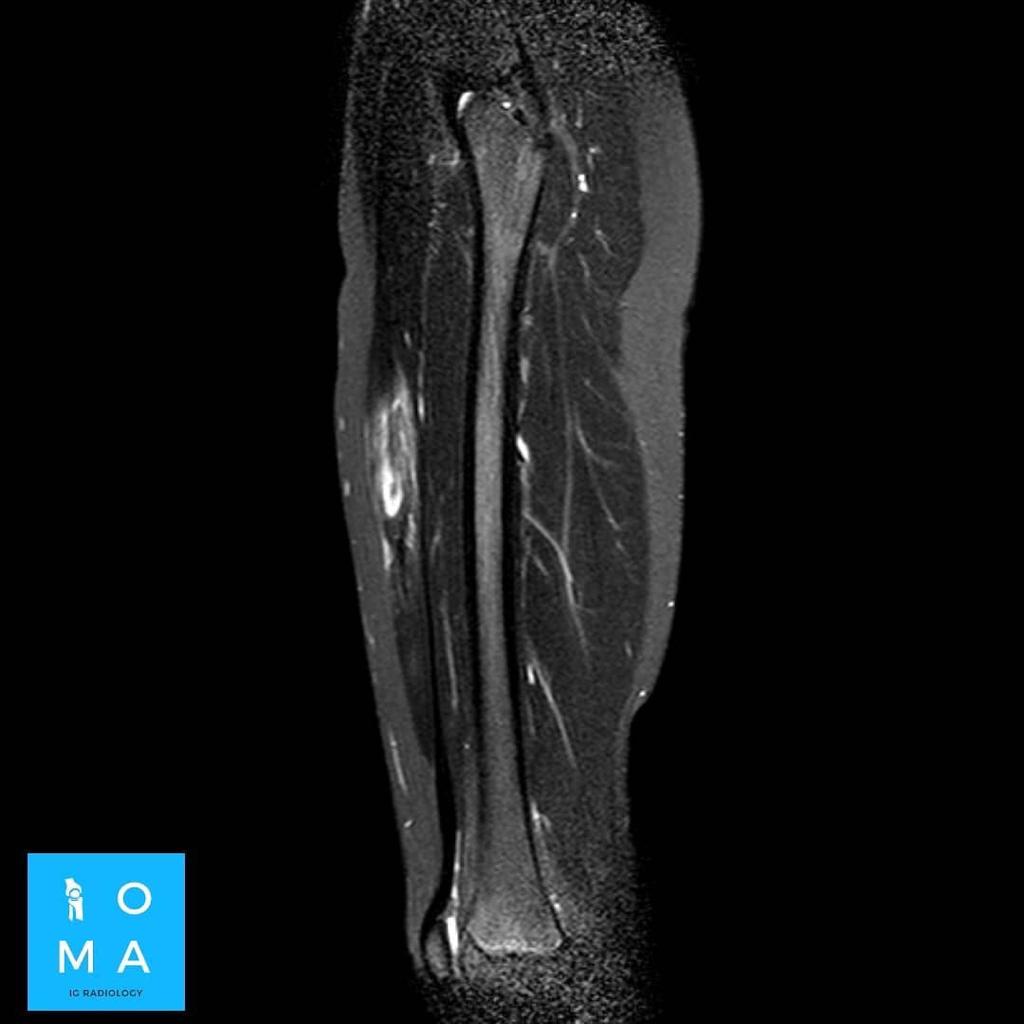

🔹Cambios inflamatorios asociado a edema y banda líquida que rodea a la unión miotendinosa central del sector medio del músculo recto anterior del cuádriceps derecho, de 10 mm de extensión, evocador de desgarro de la unión miotendinosa grado II.

.La sintomatología es poco clara, la RMN aporta información fundamental acerca de la extensión y localización (lesiones cercanas a la inserción requieren mas días de tratamiento) , sin embargo el edema sobredimenciona la lesión, por lo que el método de elección, para clasificar el grado, es la ecografía realizada por un especialista en aparato osteomioarticular.